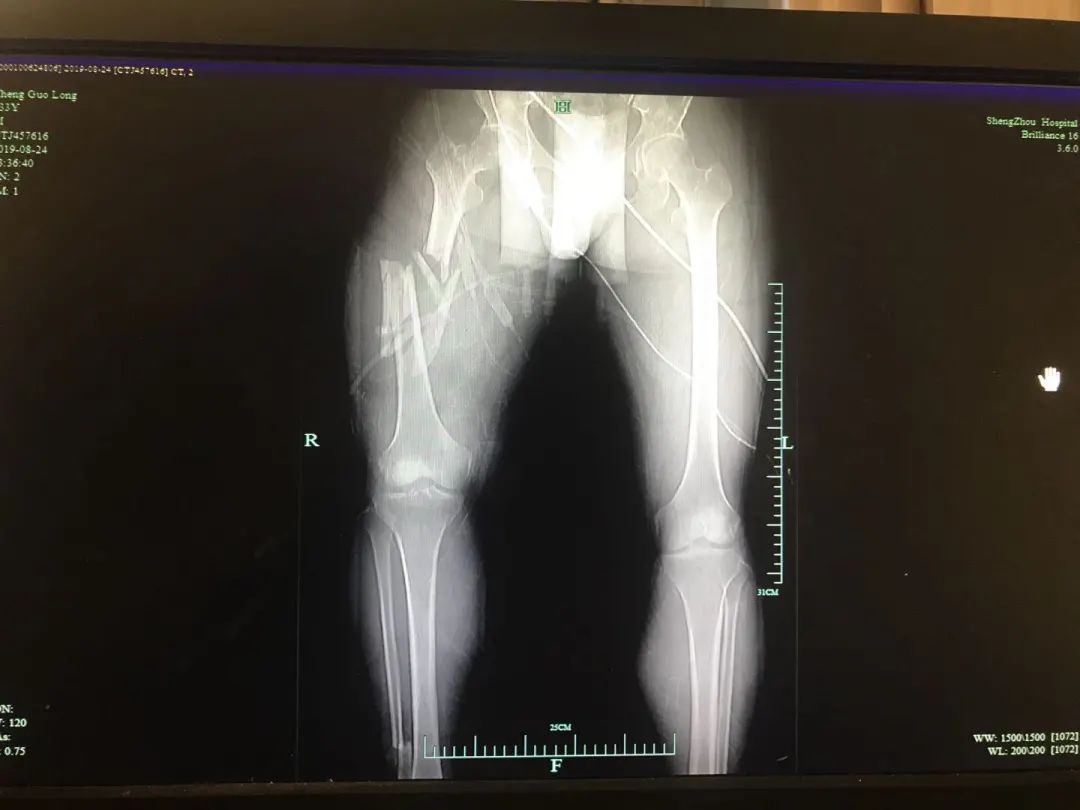

首先就是要将其右腿近十处骨折进行紧急救治。右股骨中段粉碎性骨折、右股骨颈骨折、右胫骨平台骨折、右腓骨小头骨折、右腓骨下段骨折、右髌骨骨折、开放性右踝关节骨折、右第一趾不全离断、右4、5趾缺损、右踝软组织挫裂伤……

两位骨科医师王刚祥与张伟江早已身经百战,面对受伤如此严重的右下肢还是倒吸了一口冷气。生命永远是第一位,王刚祥与张伟江立即争分夺秒为其实施紧急手术,清除伤面内坏死及污染组织、残端修整、复位、固定、缝合一项项操作有条不紊的进行,手术顺利完成。但由于邹先生伤情较重,生命体征极不平稳,且失血多,血压低,术后转入ICU继续治疗。